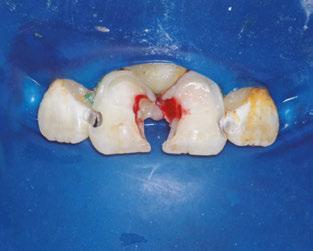

The following procedures were accomplished under general anesthesia on an outpatient basis — full mouth dental radiographs and a comprehensive oral exam. A complex odontoma was found to be the etiology of the noneruption of the maxillary right permanent central incisor (Figure 2). Since dental caries also was diagnosed, a full-mouth prophylaxis was completed. Dental caries was controlled, and teeth were restored. A 5 mm incision was made on the gingiva over the impacted maxillary right permanent central incisor, and two tooth-like structures were extracted from the right maxillary incisor area. A postoperative periapical radiograph was taken to confirm complete odontoma removal (Figure 3). Three interrupted sutures using 3-O chromic gut were placed.

Figures 2 and 3: 2. Periapical radiograph of involved area taken in the operatory during initial dental rehabilitation under general anesthesia (left). 3. Periapical radiograph of involved area taken in the operatory during initial dental rehabilitation under general anesthesia immediately after odontoma removal (right)